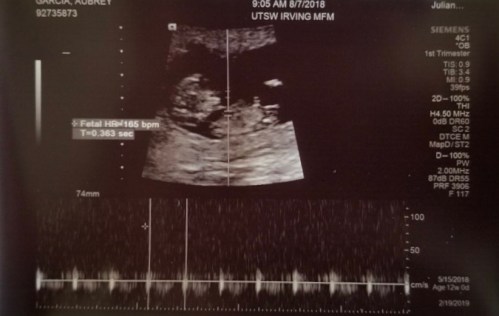

Exciting things are happening in your life right now. Hour by hour, God is involved in the process of making you and helping you grow. He is personally marking every single cell in your little body with the unmistakeable signature of His image. And although it doesn’t show up in your sonogram pics, God has already placed a crown of dignity and glory and honor on your precious little head. He loves you.

So for now, we must wait. You will be here soon. We will continue to pray for you every day as we wait for your arrival. Your mom will have lots of visits to her doctor. Your dad will call to give us updates. We look forward to seeing more sonogram pics so be sure to smile. We love you, precious little one.